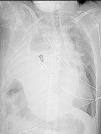

Paciente con traumatismo toracoabdominal cerrado que se complicó a las 48h con insuficiencia respiratoria. Se realizó TAC de tórax y abdomen donde se evidenció introducción de estructuras intraabdominales (lóbulo hepático derecho, vesícula biliar, grasa mesentérica, ángulo hepático del colon y asas de delgado) al interior de la cavidad torácica, asociado a colapso casi completo del parénquima pulmonar y desplazamiento de estructuras mediastínicas (figs. 1 y 2), hallazgos secundarios a extensa lesión diafragmática derecha, que obligó a la reparación quirúrgica urgente. El diagnóstico precoz de una rotura diafragmática puede pasar desapercibido, manifestándose tardíamente cuando el defecto diafragmático aumenta y se produce la herniación de vísceras abdominales a la cavidad torácica.